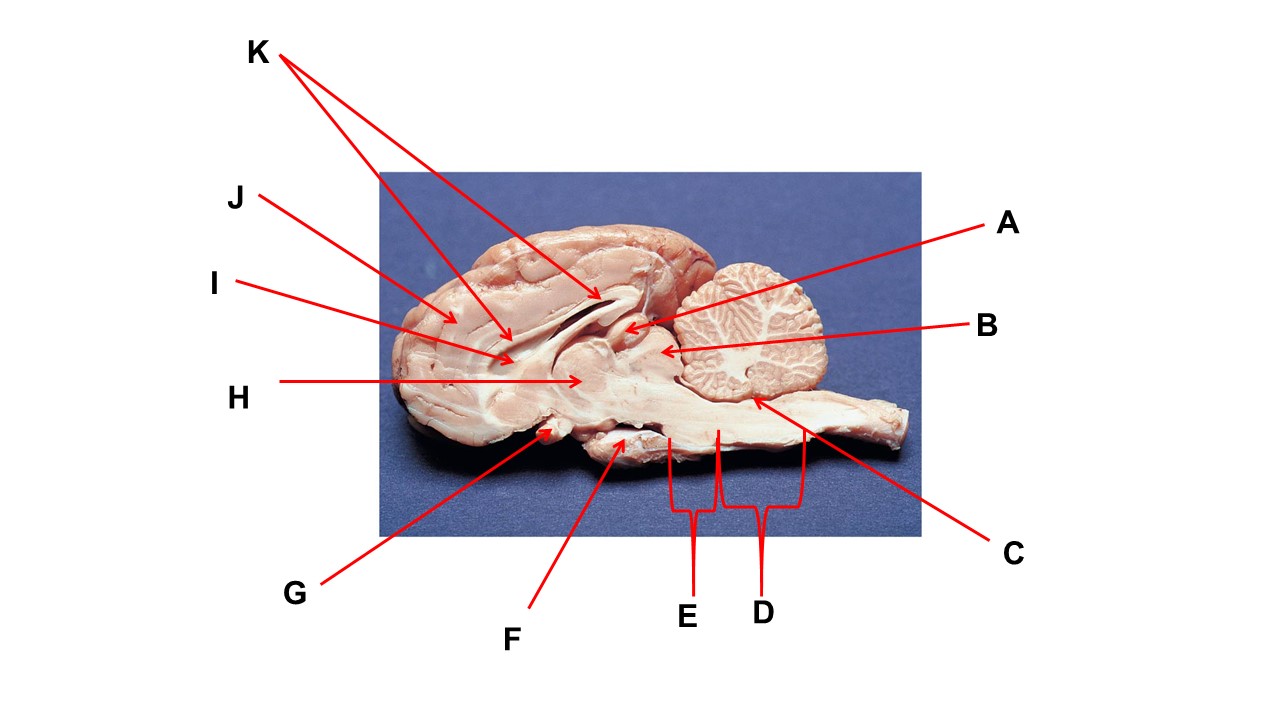

Name the structure at the tip of arrow A.

pineal gland

The cavity at the tip of arrow I is the _____.

lateral ventricular

The cavity at the tip of arrow I is filled with ______.

cerebrospinal fluid

Name the structure at the tip of arrow F

mammillary body

Name the structure at the tip of arrow A.

pineal gland

Name the structure at the tip of arrow G

optic chiasma

Name the nerve at the tip of arrow H.

optic